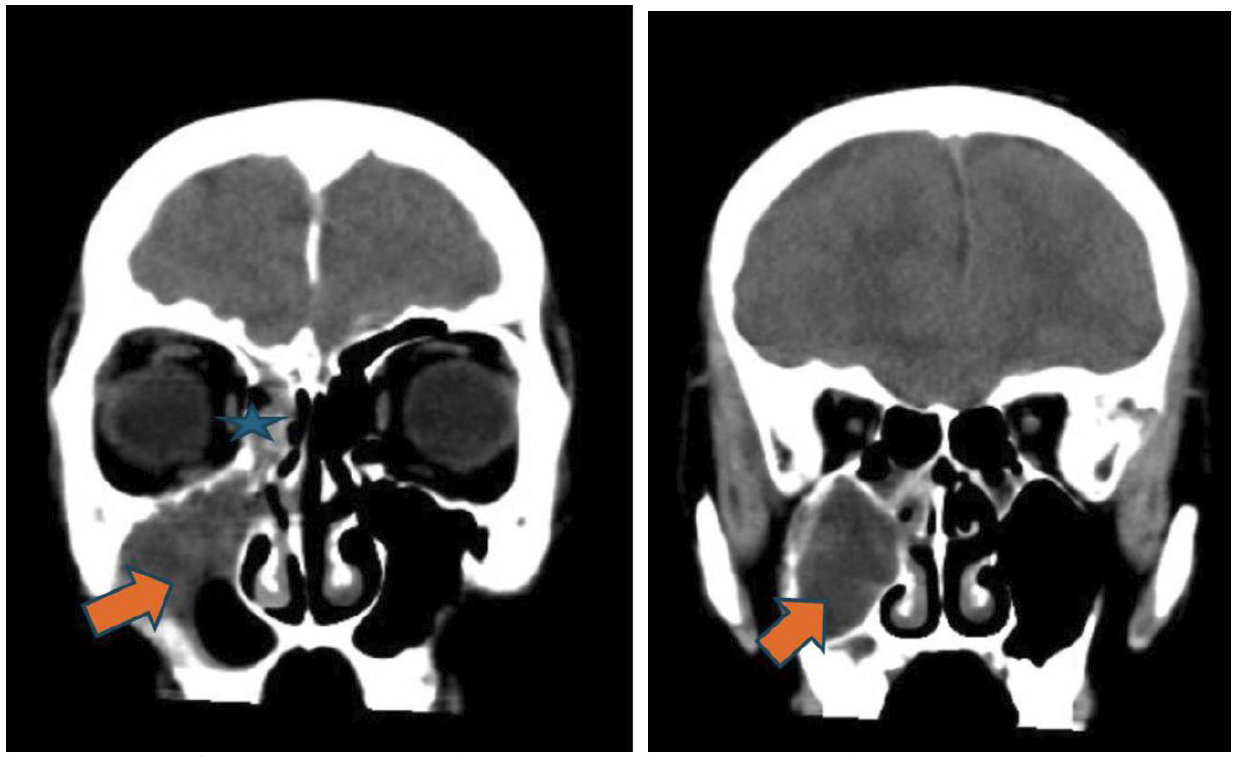

此病童的電腦影像,電腦斷層影像(非注射對比顯影劑),在冠狀切面(圖一)清楚呈現顏面部上頜竇(maxillary sinus)、鼻腔、篩竇(ethmoid sinus)、蝶竇(sphenoid sinus)等腫脹與不均值等病灶,且與健側對照,佐以軸狀切面影像,額竇(frontal sinus)的腫脹與不均值密度病灶(圖二)能較清楚呈現。進一步思考,病童呈現“雙眼球無法往左側移動”“頭痛且意識狀況異常”等,循著解剖器官組織的概念,審視眼部的影像,右眼框骨頭附近篩竇組織腫脹(圖一),審視腦部的影像,不管是軸狀面或是冠狀面影像(圖三),腦部組織腫脹且“推擠”至左側腦部呈現中線偏移。在部分腦部頂葉(parietal lobe)的影像(圖四),呈現相較低密度的“液體”狀成像,結合病童病史和抽血報告,積液部分疑似蓄膿,鑑別診斷可與慢性出血的稍高或等值密度做解析。另外,亦可藉由電腦軟體上可顯示的”Hounsfield unit, HU” 進行分析解讀。

圖四、頭部電腦斷層軸狀切面(axial view)(左圖)和冠狀切面(coronal view)(右圖):硬腦膜附近,呈現一層不均勻密度的積液(橘紅色箭頭)。

綜合病童的臨床症狀與電腦斷層結果,右側鼻竇(上頷竇、篩竇、蝶竇、額竇)皆呈現廣泛侵犯性發炎病灶,往上延伸到右側硬腦膜下蓄膿,右側腦部腫脹合併壓迫到腦室和中線偏移,疑似腦壓過高的情況。  病童在緊急處置後,轉入兒童加護病房繼續治療與監測,同時給予降腦壓藥物和後線抗生素治療,後續安排手術清除鼻竇的發炎。遺憾的是,病童在接受手術前,產生持續性癲癇發作,急救不及,瞳孔放大,雖經緊急呼吸道處置和開顱手術,於加護病房治療1個多月,依舊藥石罔效,最後腦死。